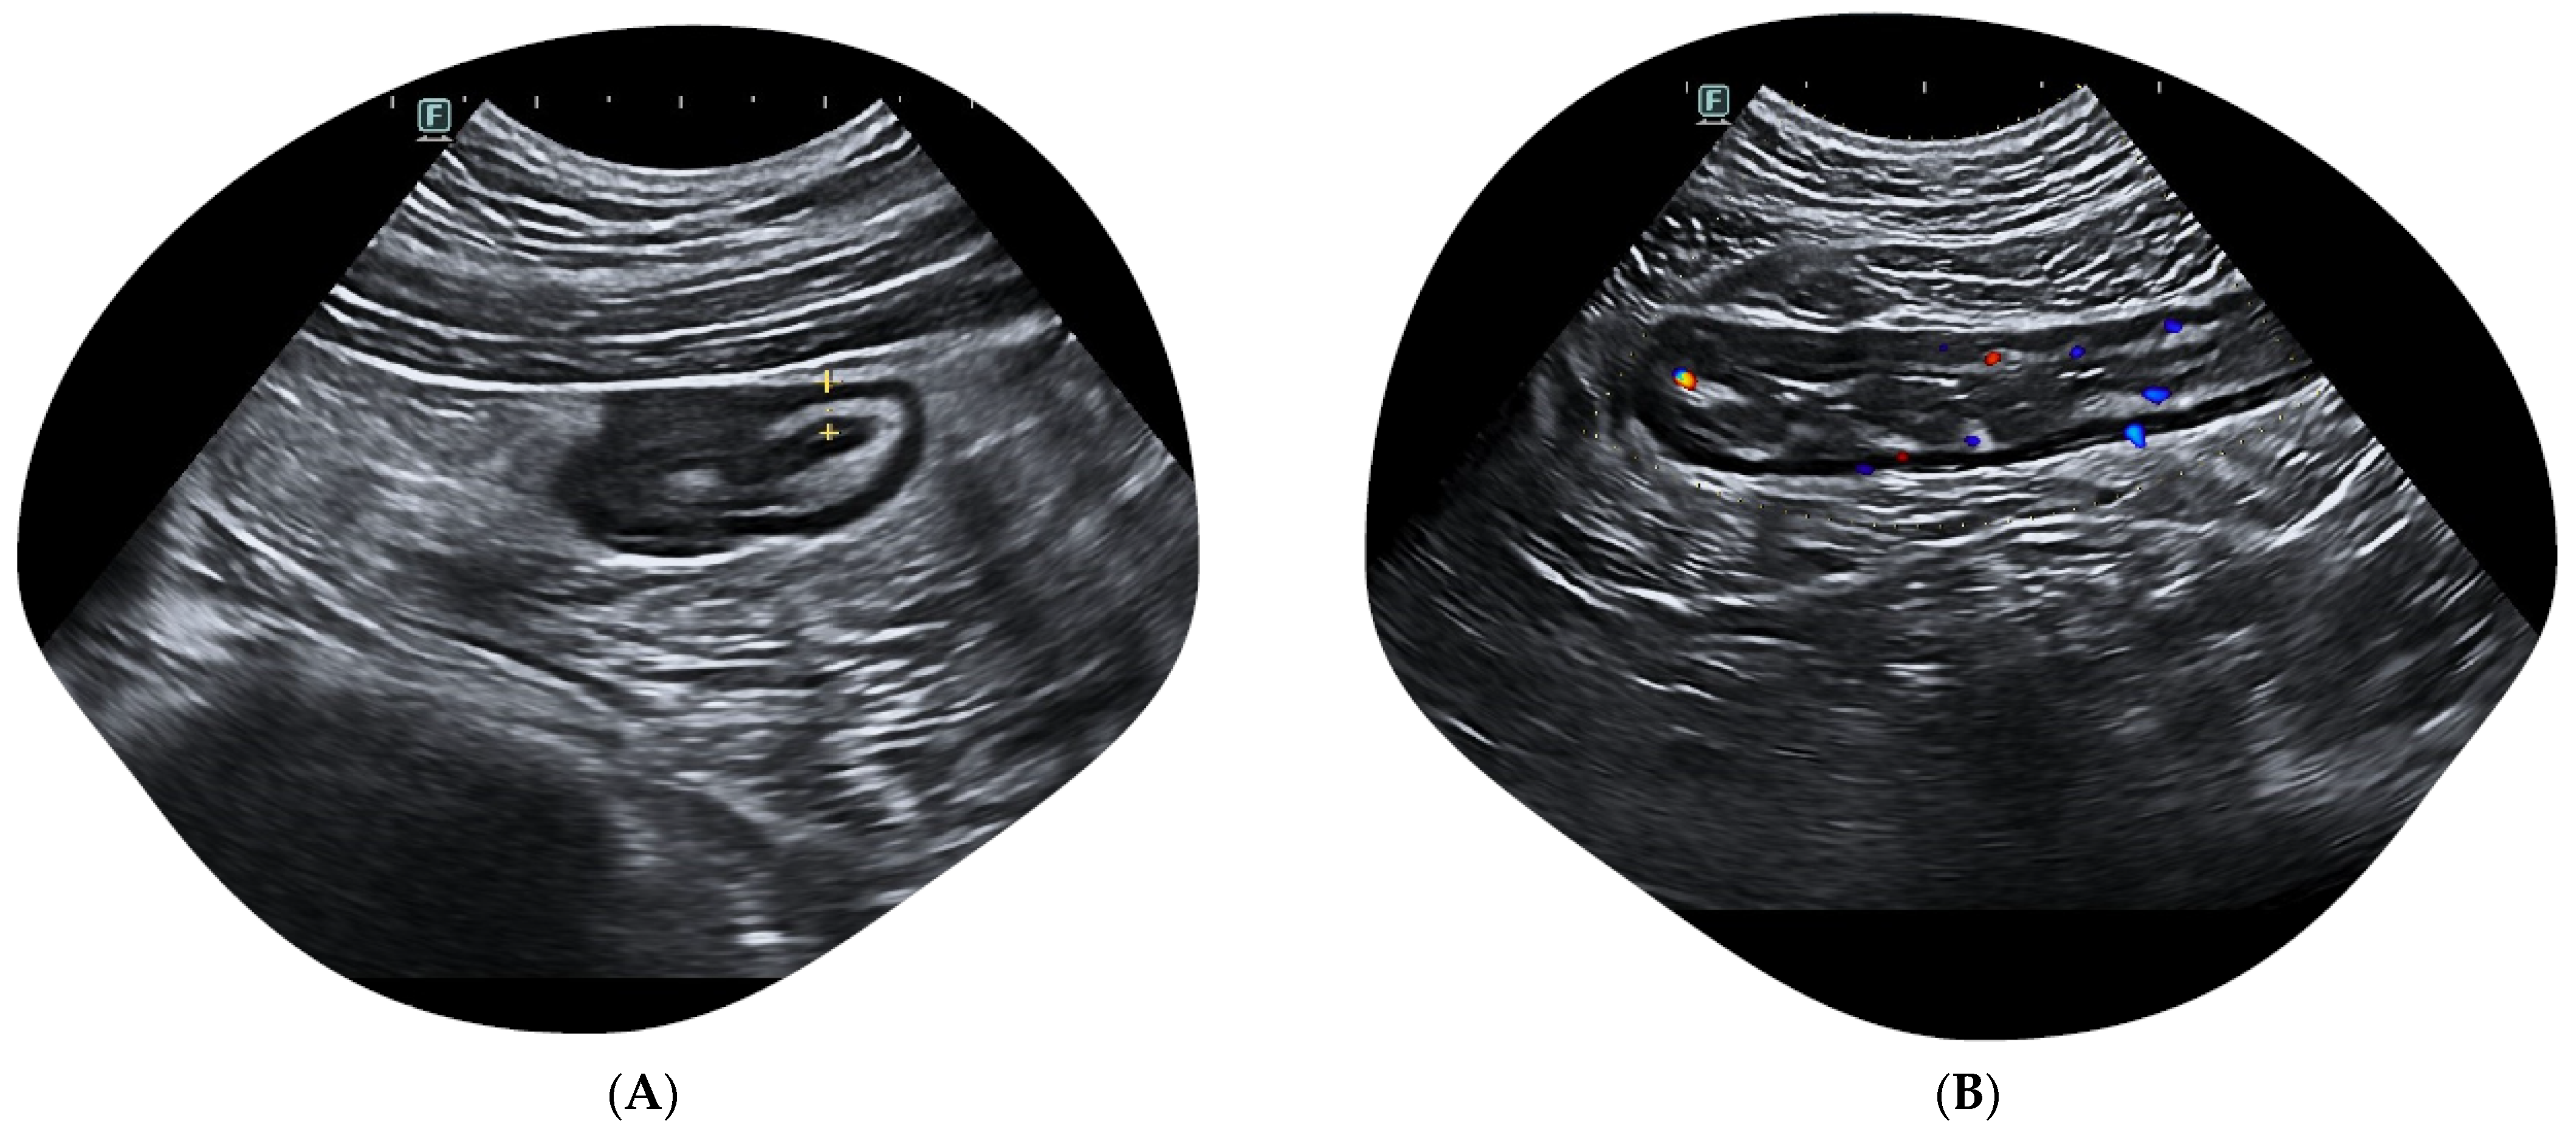

2.1. Colonic Evaluation

2.2. The Challenge of Rectum Evaluation